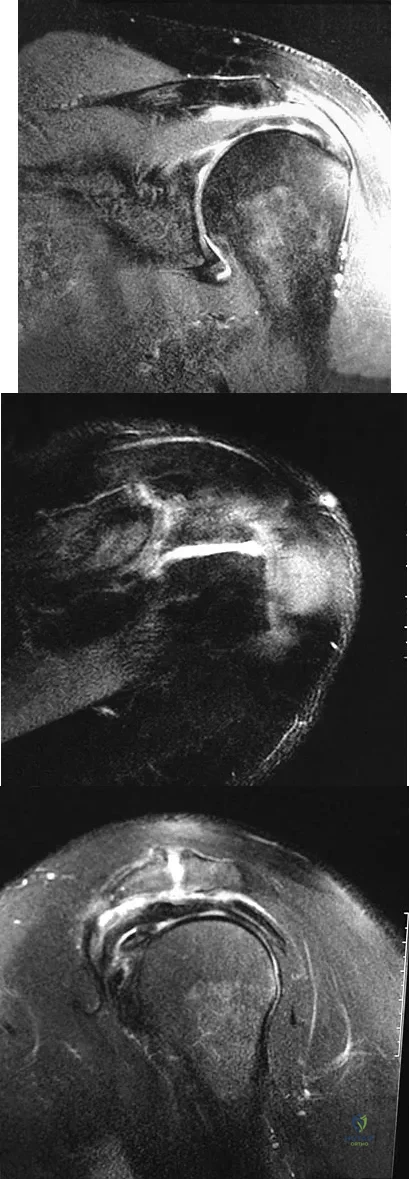

Question 54

Figures 26a through 26c show the MRI scans of a 47-year-old man who underwent arthroscopic shoulder surgery 6 months ago and continues to have pain despite a prolonged course of rehabilitation. Management should now consist of

Explanation